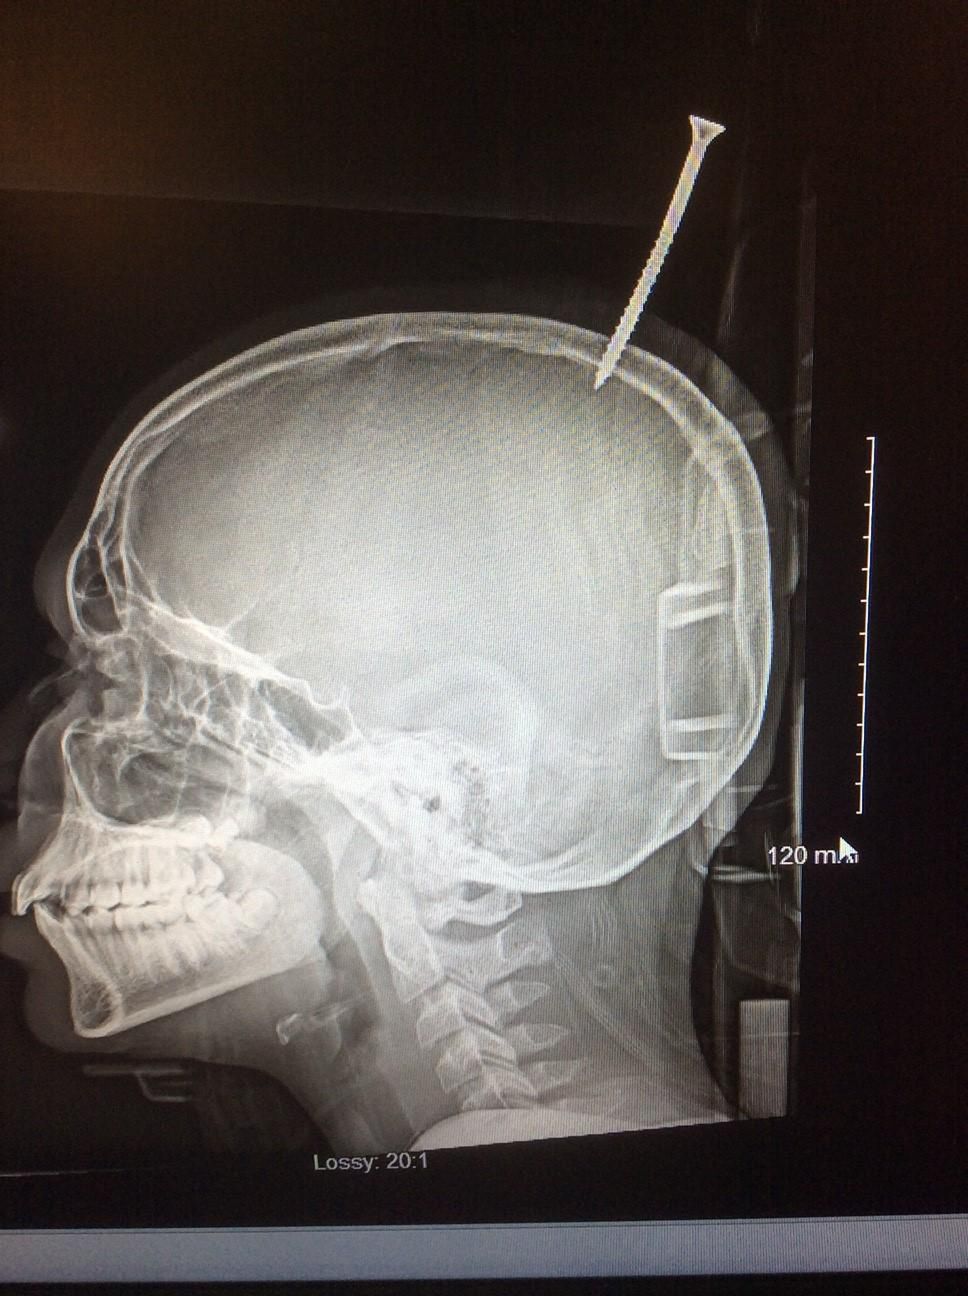

Chłopiec z Maryland w USA przeżył dziwaczny wypadek podczas budowy domku na drzewie. Media w USA opisały właśnie, jak w poprzednią sobotę 13-latka uderzyła w głowę deska, a doczepiony do niej metalowy wkręt przebił mu czaszkę. Darius Foreman konstruował swoją kryjówkę wśród gałęzi drzewa w mieście Salisbury, gdy poślizgnął się i spadł na ziemię, a wraz z nim narzędzia i deski. Jedna z nich nieomal go zabiła. - Myślę, że śmierć była dosłownie o milimetr - stwierdził dr Alan Cohen, szef neurochirurgii na wydziale pediatrii szpitala Johna Hopkinsa w Baltimore.

Dr Cohen dowiedział się od ratujących chłopca strażaków, że deska z gwoździem, która spadła na głowę Dariusa, miała ponad półtora metra długości. Zanim chłopiec trafił do śmigłowca pogotowia udało się ją znacznie skrócić. W ten sposób 13-latek nie wykrwawił się podczas transportu. - On nawet z tą skróconą deską nie był w stanie zmieścić się do pierwszego helikoptera, który przyleciał, więc wezwali drugi, większy - wyjaśnia lekarz.

Chłopca ostatecznie przetransportowano do szpitala Johna Hopkinsa. Operację przeprowadziła żona dr Cohena, która także jest dziecięcym neurochirurgiem. Pierwszym problemem było odczepienie deski od gwoździa. Gdy to się udało zrobić, zmierzono się z czymś dużo trudniejszym, czyli wyciąganiem wkrętu. - Jeżeli byśmy go dosłownie wykręcili, krew byłaby wszędzie - wyjaśnia lekarz.

Chirurdzy zdecydowali się wyciągnąć wkręt, manipulując nim z boku, od środka czaszki. Wywiercili dwa otwory w głowie chłopca, z lewej i prawej strony wkrętu. Dzięki temu uzyskali dostęp do jego czubka. Uniknięto ryzykownego krwawienia, a otwory w głowie dziecka zasłonięto tytanowymi płytkami.